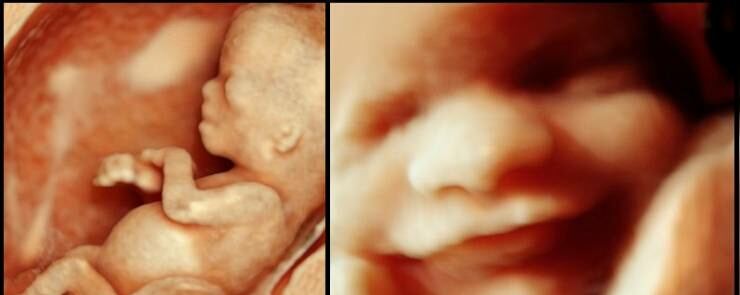

- الجنين يبتسم في بطن أمّه، وذلك من سلسلة تعابير الوجه التي يقوم بها، إذ ليس من المستبعد أن يرسم ابتسامة عريضة على وجهه، الظاهرة التي تمّ إلتقاطها في عدّة صور بتقنية الـ3D.

- الجنين يفتح عينيه في بطن أمه ويرمش أيضاً! هذا الأمر لا يحدث إلاّ في المراحل المتقدّمة من الحمل، علماً بأنّ حاسّة النظر هي آخر حاسّة تتطور وتنضج لديه.